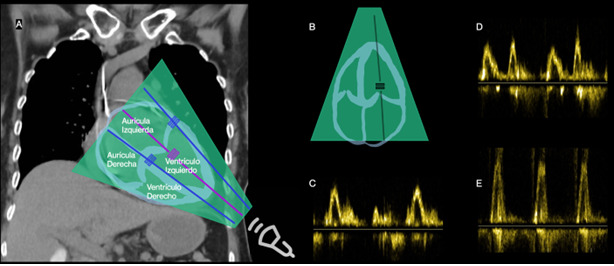

Heart failure (HF) is a clinical syndrome with symptoms and/or signs caused by structural and/or functional cardiac abnormalities. After discharge, patients with acute heart failure (AHF) face a significant risk of rehospitalization and mortality. Detection of residual congestion is crucial to reduce readmissions, improve prognosis, and decrease mortality. Echocardiography provides critical information about the severity of left ventricular dysfunction, elevated filling pressures, valvular dysfunction, and estimation of pulmonary artery systolic pressure. The VExUS approach integrates ultrasound evaluation of the inferior vena cava, hepatic veins, portal vein, and renal veins, providing valuable information about systemic congestion. Lung ultrasound detects pulmonary congestion, facilitating early intervention to prevent progression and hospitalizations. Ultrasound evaluation of the internal jugular vein and femoral vein complements the evaluation of venous congestion. Distension of the internal jugular vein during the Valsalva maneuver or the relationship between the diameter of the internal jugular vein and the femoral vein can predict adverse outcomes in patients with HF. In conclusion, a comprehensive ultrasound approach is crucial in the management of patients with critically ill heart failure. Multiparameter ultrasound evaluation provides vital information, guiding appropriate therapeutic interventions and avoiding potentially harmful measures.